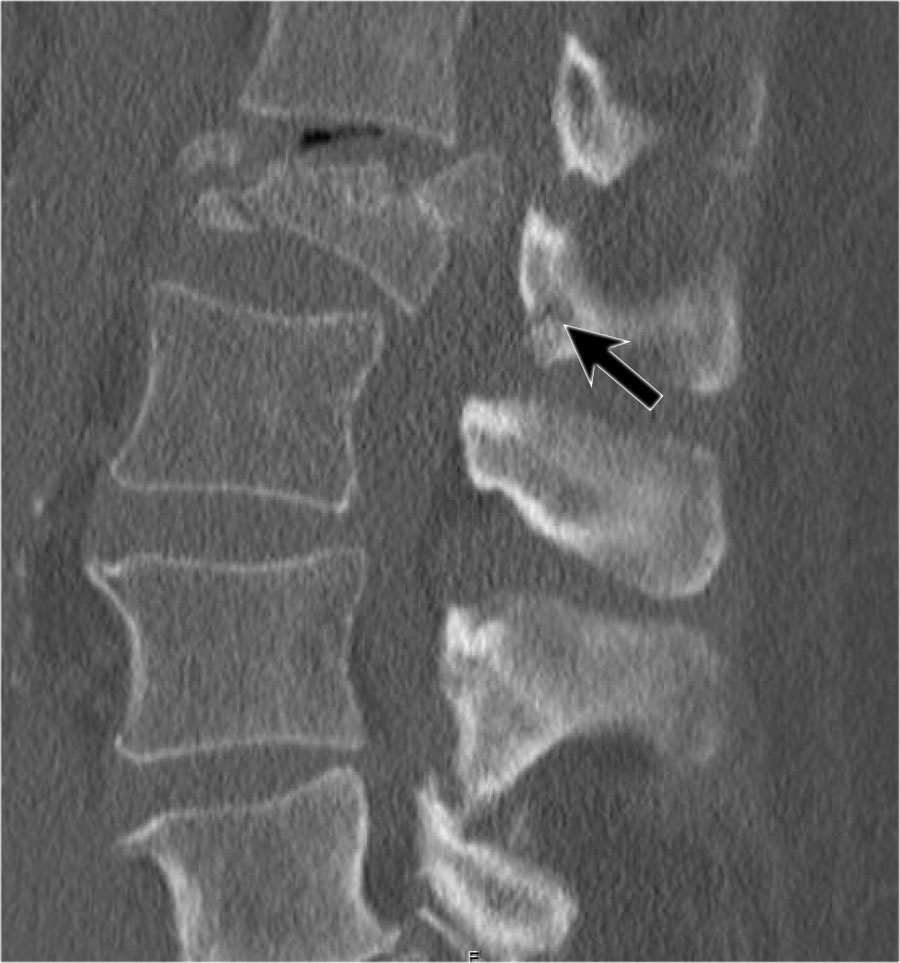

Mảnh xương góc sau trên thân đốt sống bị đẩy lùi ra sau (Retropulsion)

Hiện tượng mảnh xương bị đẩy lùi ra sau là đặc điểm điển hình của gãy vỡ, phân biệt rõ ràng với gãy nén đơn thuần.

Cuộn qua các hình ảnh.

Gãy theo mặt phẳng đứng dọc của thân đốt sống và

cung sau đốt sống

Gãy theo mặt phẳng đứng dọc của thân đốt sống và gãy cung sau theo mặt phẳng đứng dọc gặp lần lượt trong 90% và 85% các trường hợp gãy vỡ.

Dưới đây là bốn ví dụ minh họa.

Trong phân loại Denis, đây sẽ là gãy ba cột — trước/giữa/sau — cho thấy gãy xương rất không vững.

Tuy nhiên, trong phân loại TLICS, đây là gãy vỡ, tức là 2 điểm cho hình thái.

Phương pháp điều trị sẽ phụ thuộc vào tính toàn vẹn của PLC và tình trạng thần kinh.